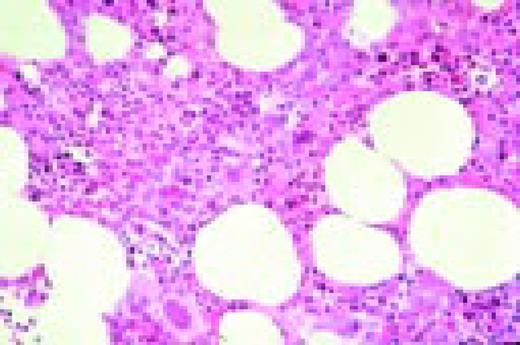

Burkitt's lymphoma. Composite: bone marrow biopsy (L) and bone marrow aspirate (R). Giemsa stained. This 19-year-old male presented with a submandibular tumor in 1997. A biopsy revealed non-Hodgkin's lymphoma, Burkitt's type, according to the REAL classification. Staging revealed stage I disease. He was treated with aggressive polychemotherapy for Burkitt's lymphoma and an allogeneic bone marrow transplant was planned for March 1998. Two weeks before BMT, the patient complained of back pain, and there was a sharp rise of LDH. A bone marrow smear and biopsy revealed massive infiltration by Burkitt lymphoma blasts. Few tumor cells were seen in the blood smear. The slide (R) shows typical Burkitt's lymphoma with vacuolated cytoplasm (ALL-L3 blasts according to the FAB classification). The bone marrow biopsy (L) also shows the typical, leukemia type, interstitial infiltration, leaving the fat cells intact.FIG35